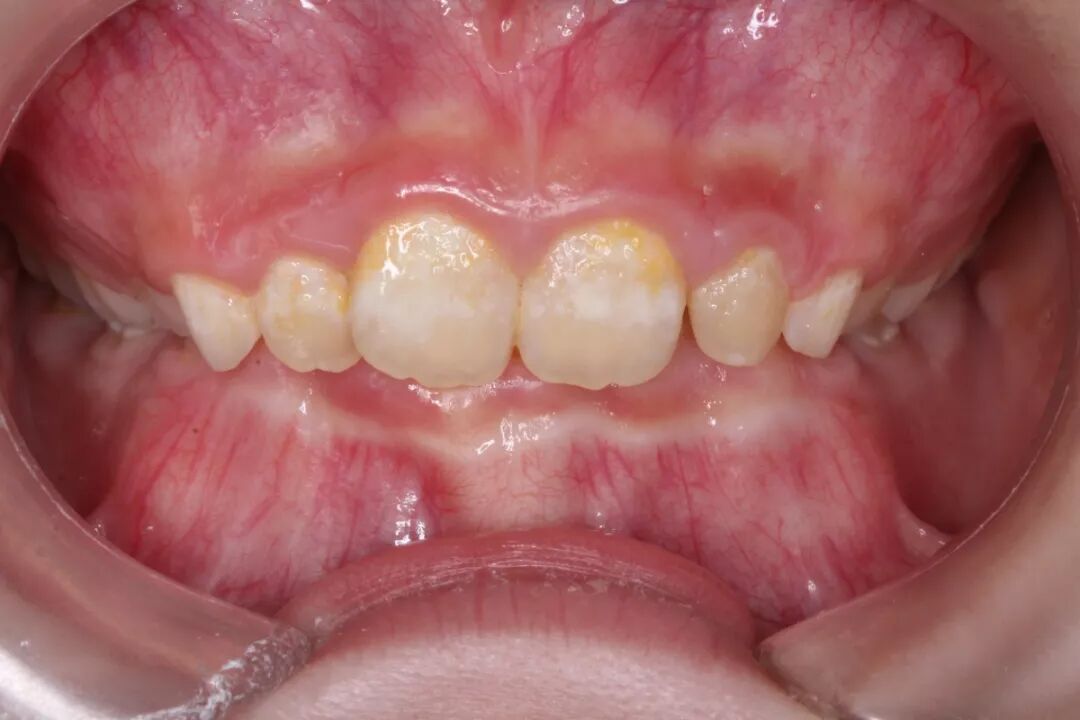

当小朋友咬住上嘴唇时,下颌需要向前伸,让下前牙咬在上前牙的前方,上前牙受到向内的力量,下前牙受到向外的力量。长此以往,上前牙往内倒,下前牙往前移,容易导致地包天。

当小朋友咬住下嘴唇时,下嘴唇会对上排牙齿产生压力,将上前牙向外推出,时间久了,上下排牙齿咬合时就会出现缝隙,产生上前牙向前突出,出现龅牙一类的状况。

有些孩子因为咬上唇的不良习惯,影响到牙齿的排列和咬合,形成了错颌,也就是大家常说的地包天。 如果家长们发现孩子有不良习惯,还是尽快带宝贝“跟牙医做朋友”吧。避免影响到小患者的口腔健康,乃至影响到面部骨骼的发育。